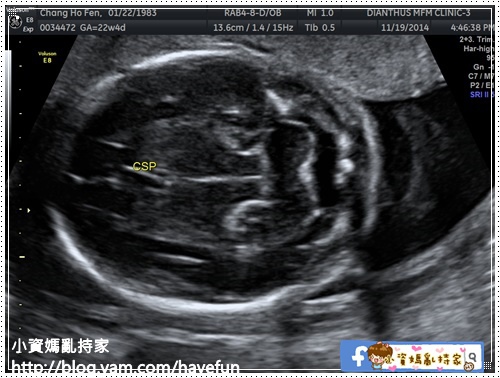

CSP透明中隔

VP側腦室寬度:6.34MM

MCA中腦動脈血流

BPD兩頂骨距:5.44CM

OFD枕骨額骨距:7.24CM

HC頭圍:20.02CM

Cereb小腦長:2.47CM

CM腦室大池:4.08mm